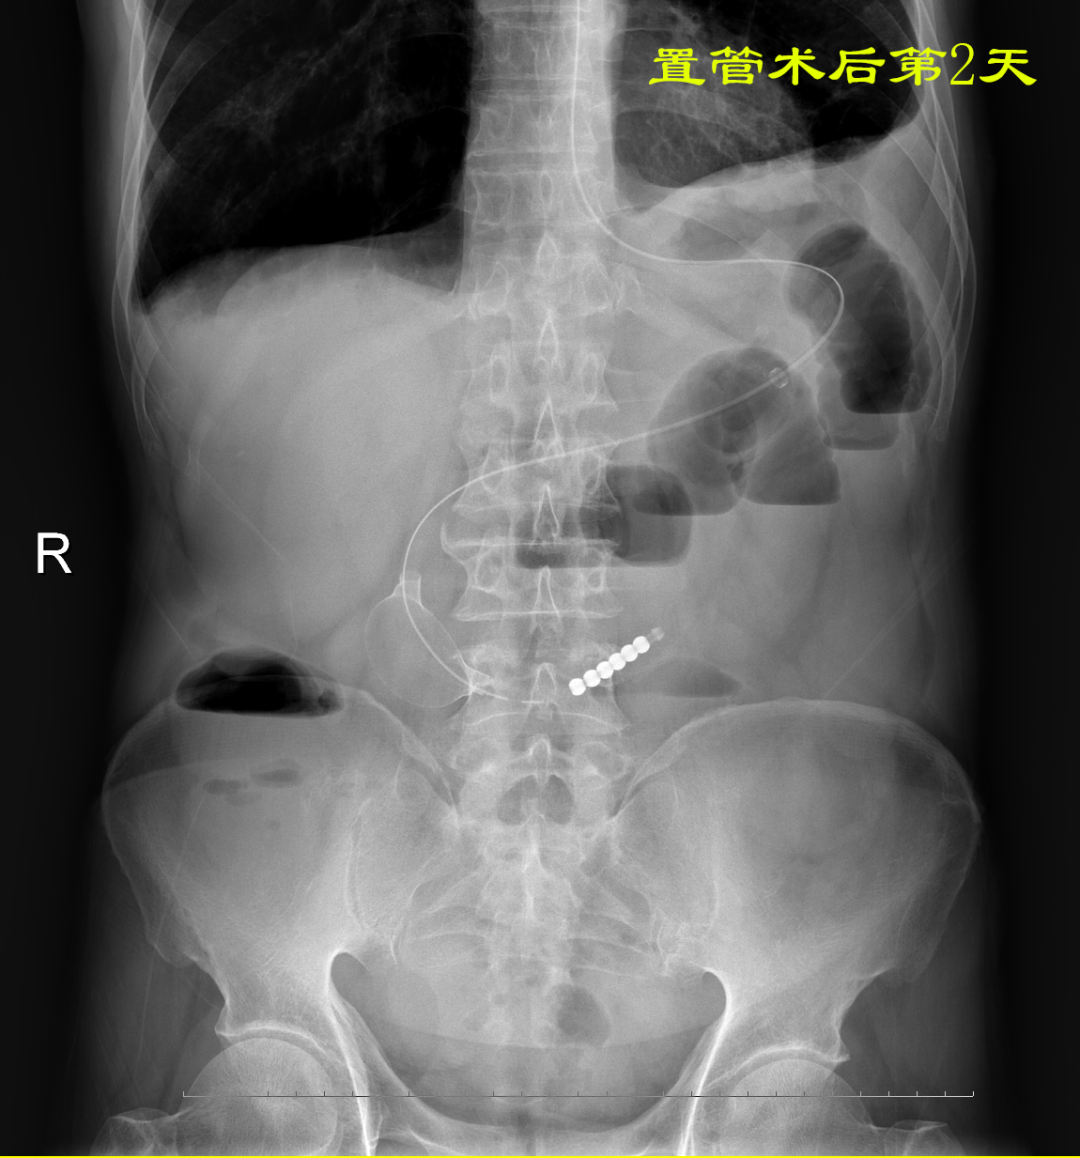

病例:患者男性,74岁,因“腹痛、腹胀伴呕吐、肛门停止排气排便20小时”于2021年7月24日入住我院普外科。患者1月前因回肠穿孔于我院普外科手术治疗,入院后明确诊断为术后粘连性小肠梗阻,经胃管引流等保守治疗无好转。因患者有严重心肺疾患,再次手术风险较大,并且术后再发粘连性肠梗阻的可能性也很大。经过与患者家属沟通后,最后决定采用胃镜引导下置入经鼻插入型肠梗阻导管技术来治疗肠梗阻。由我院消化内科副主任医师杨开余完成操作,耗时大约40分钟,患者术后第5天开始排气排便,腹痛、腹胀症状迅速消失,术后第7天拔除肠梗阻导管,恢复饮食。拔管至今已10天,患者已出院。随访患者无腹痛、腹胀,排便正常。

良好的引流是治疗肠梗阻的基本措施,低位小肠梗阻置入胃管引流常难以奏效,以往大多需要再次手术,而再次手术后粘连的几率高达70%。经鼻插入型肠梗阻导管就是将一根3米多长,内有四个腔道的管道置入十二指肠后,在重力和肠道蠕动的作用下,导管先端部将自动向前运动,直至到达梗阻部位。在导管到达梗阻部位后,可进行双对比造影检查了解狭窄病因,也可以对狭窄处进行扩张,还可以作为支架起到肠排列的治疗效果。肠梗阻导管治疗小肠梗阻属于微创型手术,具有痛苦小、疗效好、费用低、预防再次粘连等优点。